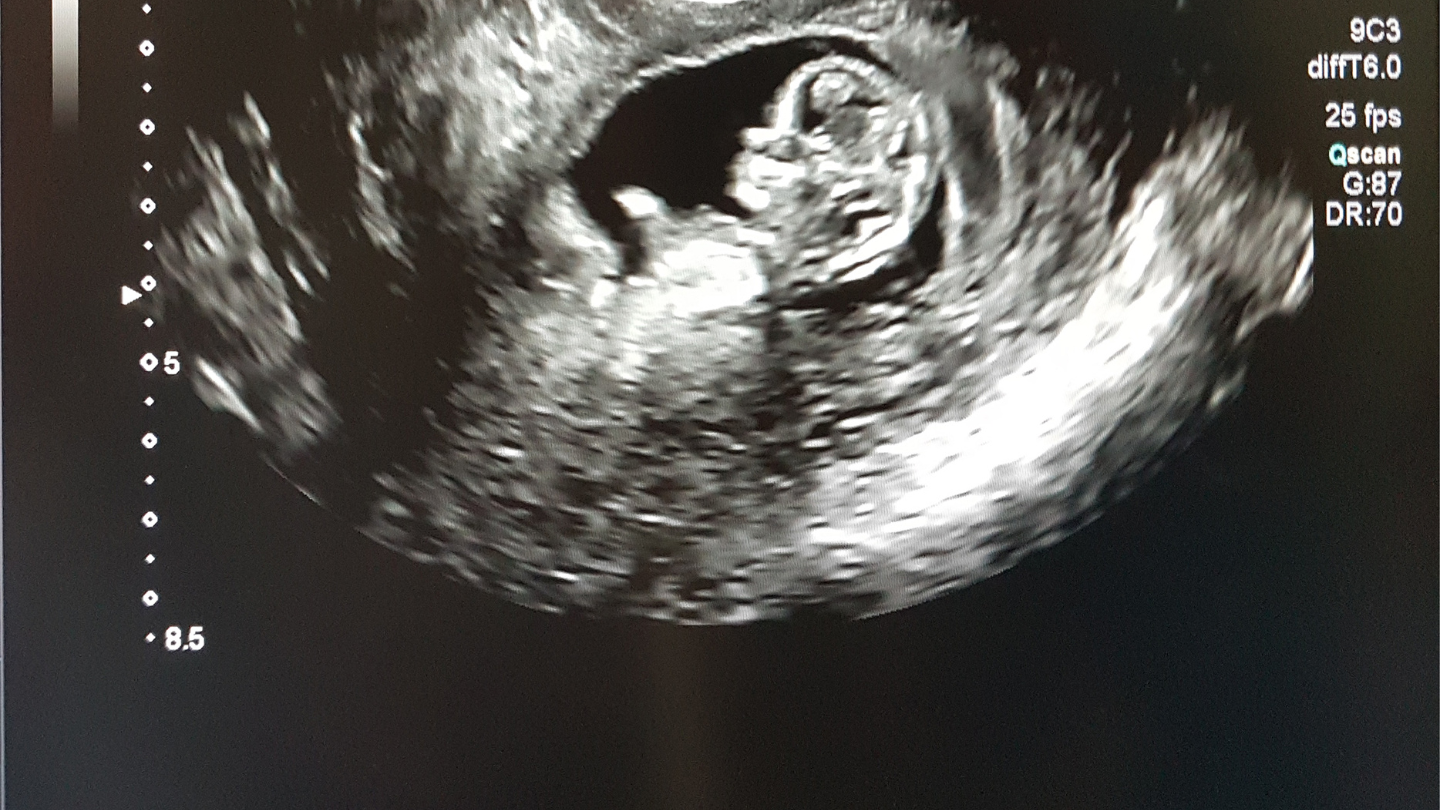

Trong thai kỳ, siêu âm là một công cụ thiết yếu trong chăm sóc tiền sản, giúp xác định tuổi thai, kiểm tra tim thai, vị trí thai và phát hiện sớm các bất thường. Tuy nhiên, việc siêu âm nhiều trong 3 tháng đầu có bị sao không là câu hỏi khiến nhiều mẹ bầu băn khoăn. Liệu sóng siêu âm có gây hại cho phôi thai đang phát triển? Tần suất siêu âm bao nhiêu là hợp lý? Bài viết này sẽ cung cấp thông tin chi tiết để giải đáp những lo ngại của mẹ bầu.

Siêu âm thai không gây hại cho mẹ và thai nhi nếu được thực hiện đúng kỹ thuật, đúng chỉ định và với tần suất hợp lý. Mẹ bầu nên thực hiện ít nhất một lần siêu âm trong 3 tháng đầu để xác định tuổi thai, vị trí làm tổ của thai và kiểm tra tim thai.

- Tuần 6 – 10: Xác định tuổi thai, kiểm tra tim thai và vị trí thai (trong tử cung hay ngoài tử cung).